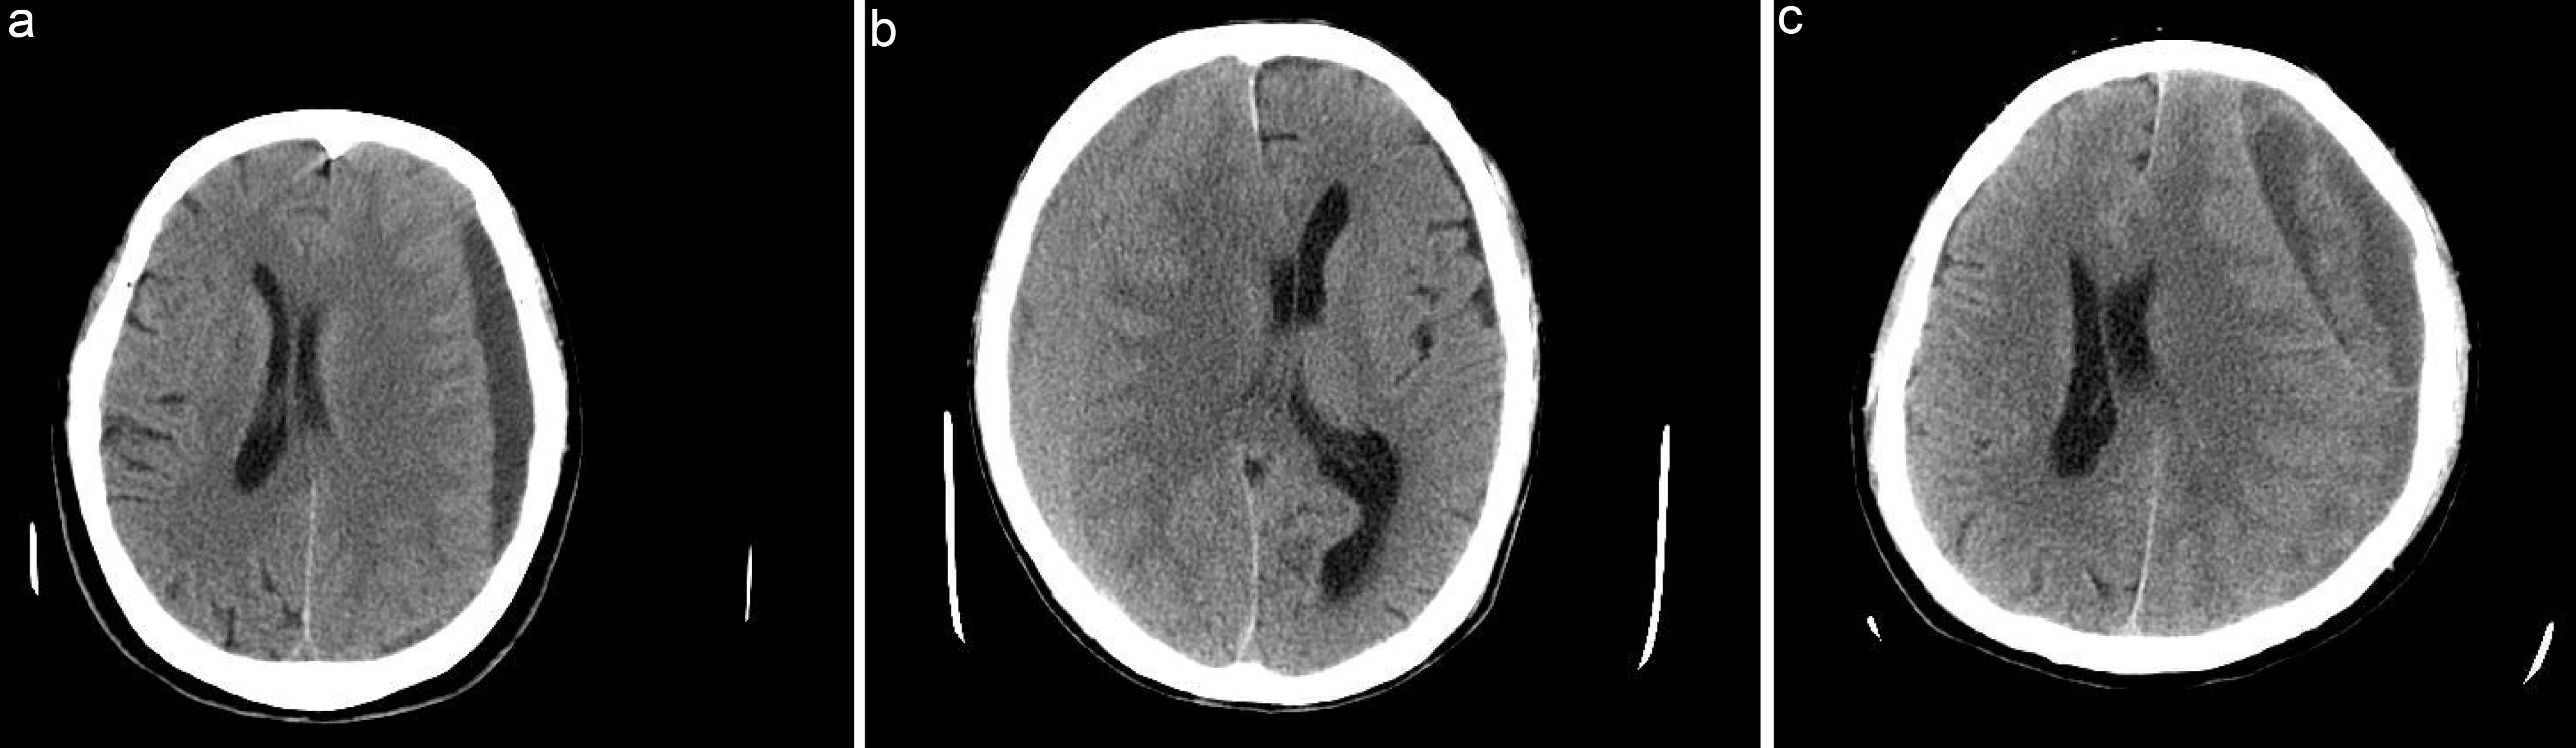

Brain computed tomography (CT) has become the examination of choice for patients with CSDH and is usually used for diagnosis and follow-up.3,19 CSDH typically presents as hypointense, isointense, or mixed-density lesions on CT, which are important for selecting the appropriate treatment (Fig. 2).20

Computed tomography images of chronic subdural hematoma.

Fig. 2  Computed tomography images of chronic subdural hematoma.

Typical computed tomography images of chronic subdural hematoma with hypodensity (a), isodensity (b), or mixed density (c).